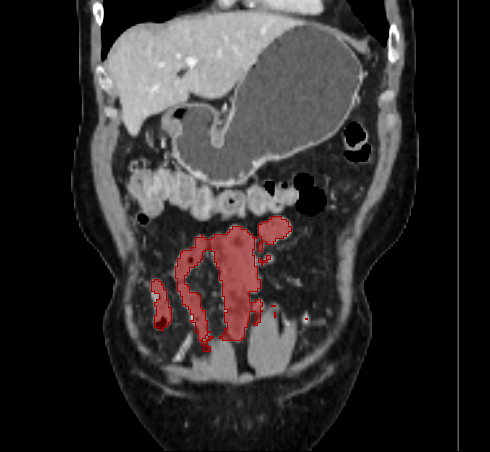

3.2 Qualitative Evaluation

Figure 3 shows example segmentation results in 3D. The result corresponding to ‘feat. & out. level DA’ in Table 1 is compared to ours. We note that the only difference between them is whether the feature disentanglement is involved for the domain adaptation, thus could show its effectiveness. Fewer errors are observed for the proposed method. We believe this is because the proposed method explicitly concentrates on the features more transferable across the datasets, the non-intensity features in this work, by disentangling those features and applying adversarial learning directly to them during the adaptation process. Example reconstruction results from the auto-encoding architecture as well as segmentation results in coronal view can be found in supplementary material.